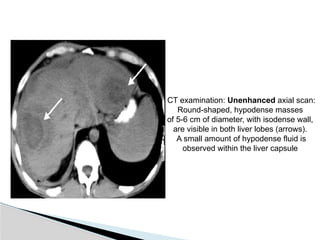

CT examination: Unenhanced axial scan:

Round-shaped, hypodense masses

of 5-6 cm of diameter, with isodense wall,

are visible in both liver lobes (arrows).

A small amount of hypodense fluid is

observed within the liver capsule